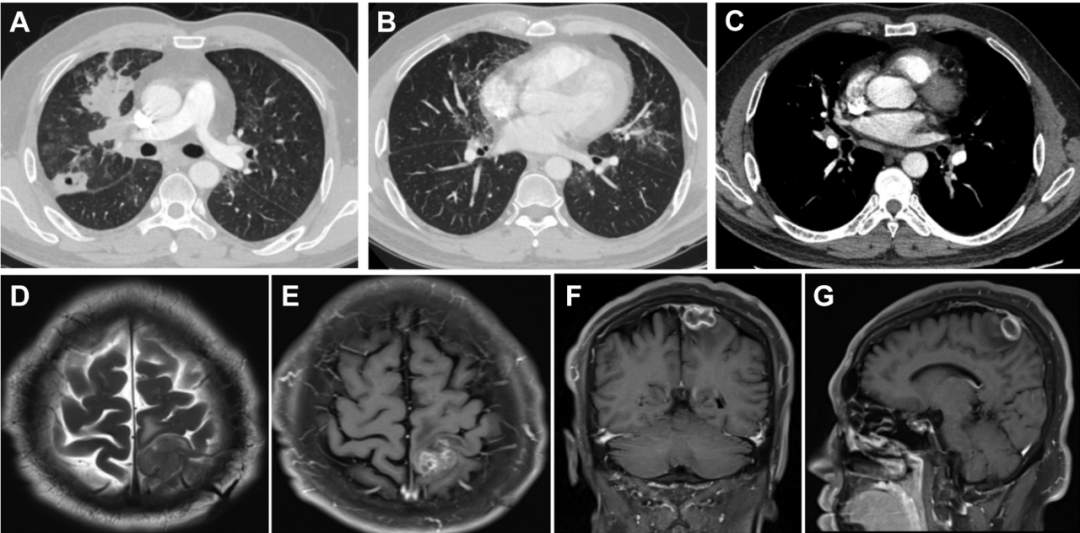

入院时胸部CT造影剂显示右上叶前段和后段有厚壁腔病变,弥漫性小叶间隔增厚与多个磨玻璃影,可见两肺疯狂铺路石征;右上肺静脉及分支可见充盈缺损(图2A-C)。

脑磁共振造影显示在左侧顶至枕叶有一个30*30*20mm异常信号(图2D-G)。